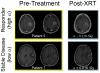

Response to therapy is conventionally assessed by determining changes in gross tumor volume (GTV) on MRI prior to and after the administration of therapy. Post-contrast T1-weighted MRI images are shown for two glioblastoma patients that would typically be separated into generic groups: responder and stable disease. Radiation response parameter α gives an additional quantification of radiation response for each patient.